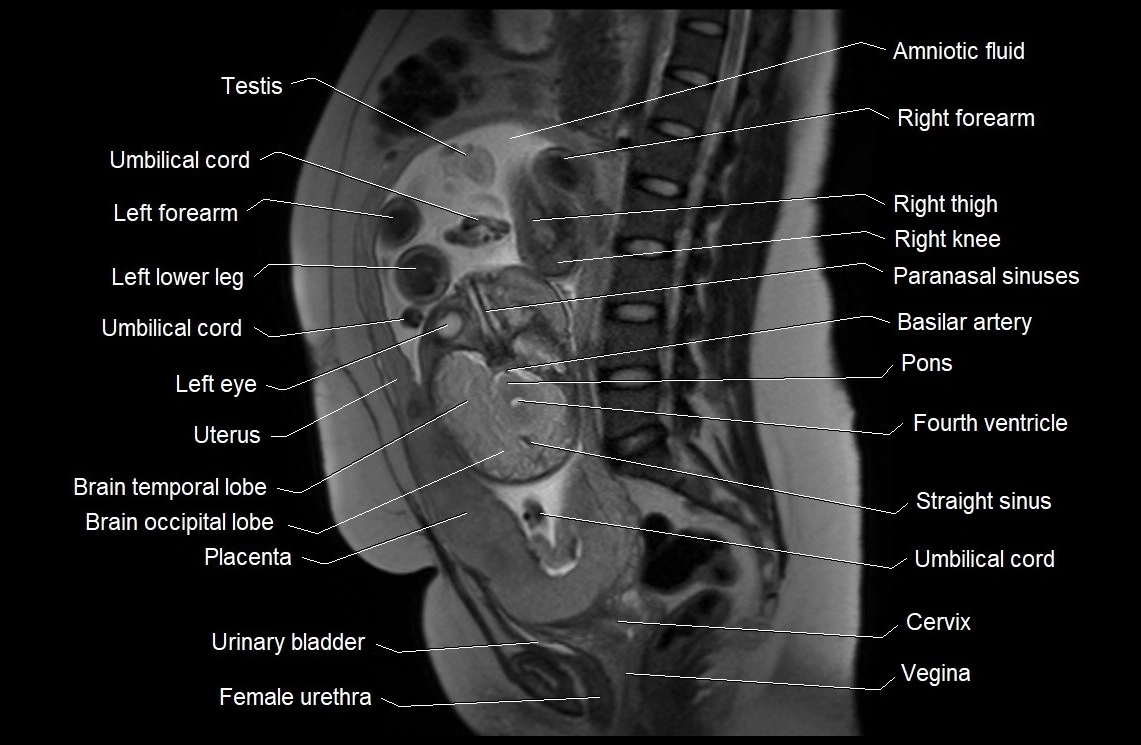

MRI Appearance

T2 HASTE (T2 GRE):

• Amniotic fluid shows very bright hyperintense signal

• Provides natural contrast against fetus and placenta

• Small particles (vernix) may appear as scattered hypointense foci within bright fluid

MRI image

image